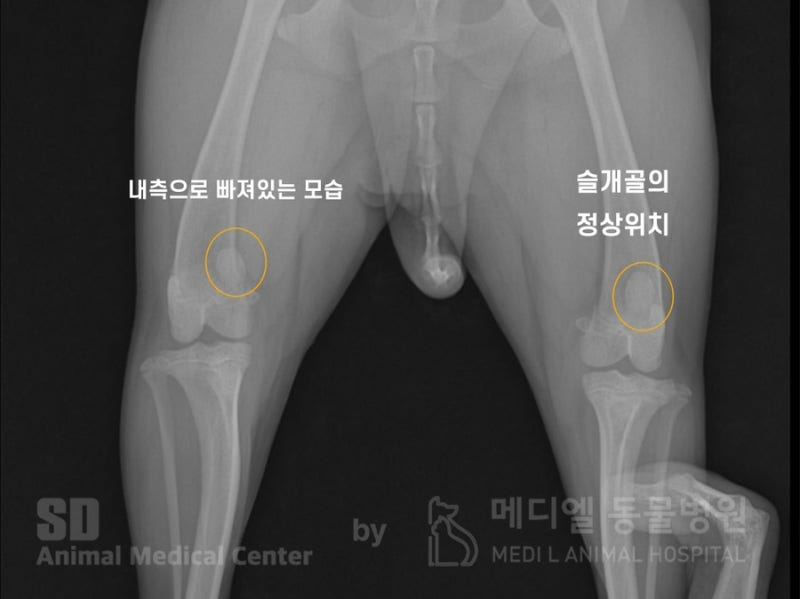

만지면 아파할 정도로 통증이 심했고, 병원에서 방사선 검사를 진행 한 결과, 우측 슬개골 탈구 2~3기로 진단받았습니다.

해당 환자의 방사선 사진입니다. 우측다리의 슬개골은 내측으로 빠져있는 것이 확인되며, 좌측 다리의 슬개골은 정상위치에서 확인됩니다.